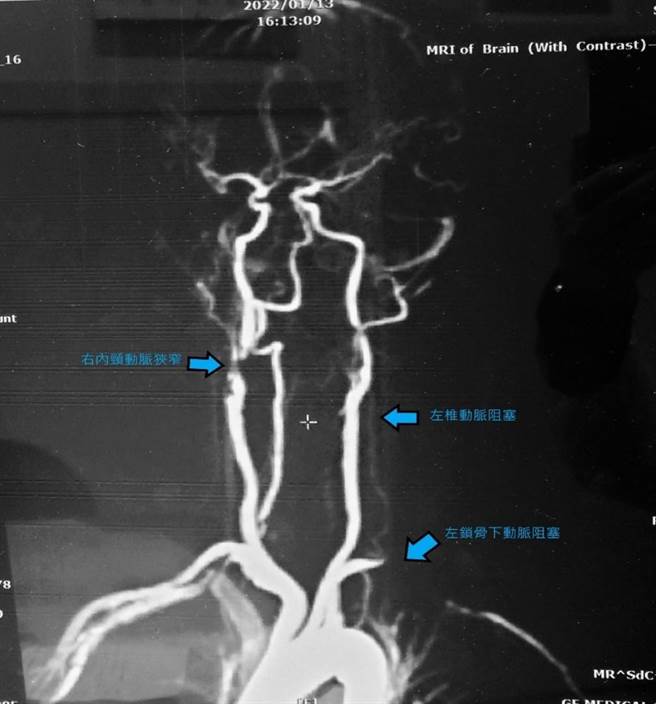

一位70岁老妇因左锁骨下动脉血管阻塞、左椎动脉阻塞、前循环的右内颈动脉狭窄,一转头就头晕昏倒,经诊断后发现是「弓箭手症候群」作祟。(高市民生医院提供/袁庭尧高雄传真)

民生医院神经内科主任曾静娟表示,「弓箭手症候群」是一种危险的头晕,如同发生在弓箭手拉弓瞄准要转头的时候的姿势,又称为转头性椎动脉症候群。老妇两手血压相差很大,平均收缩压相差30mmHg,经磁振造影检查后,发现左锁骨下动脉血管阻塞、左椎动脉阻塞,另外还有前循环的右内颈动脉狭窄等三个病灶,导致往左、左上看的时候昏厥。